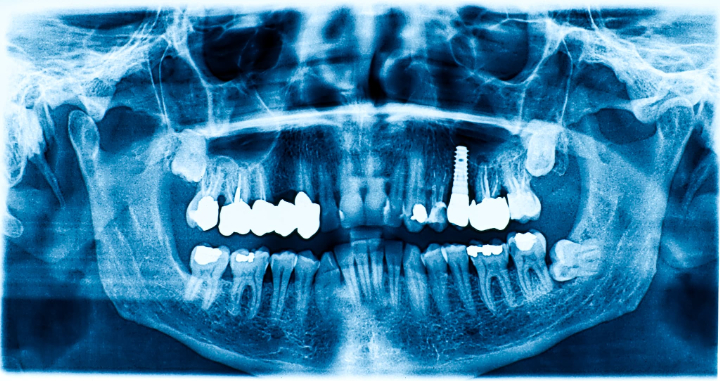

インプラント治療とは、歯を失った部分のあごの骨に人工の歯根(インプラント体)を埋め込み、その上に人工の歯を装着する治療法です。従来の入れ歯やブリッジと異なり、他の歯に負担をかけずに単独で歯を補えることが大きな特徴です。

人工歯根はチタンやチタン合金といった生体親和性の高い素材で作られており、あごの骨としっかり結合することで安定した噛み心地を実現します。